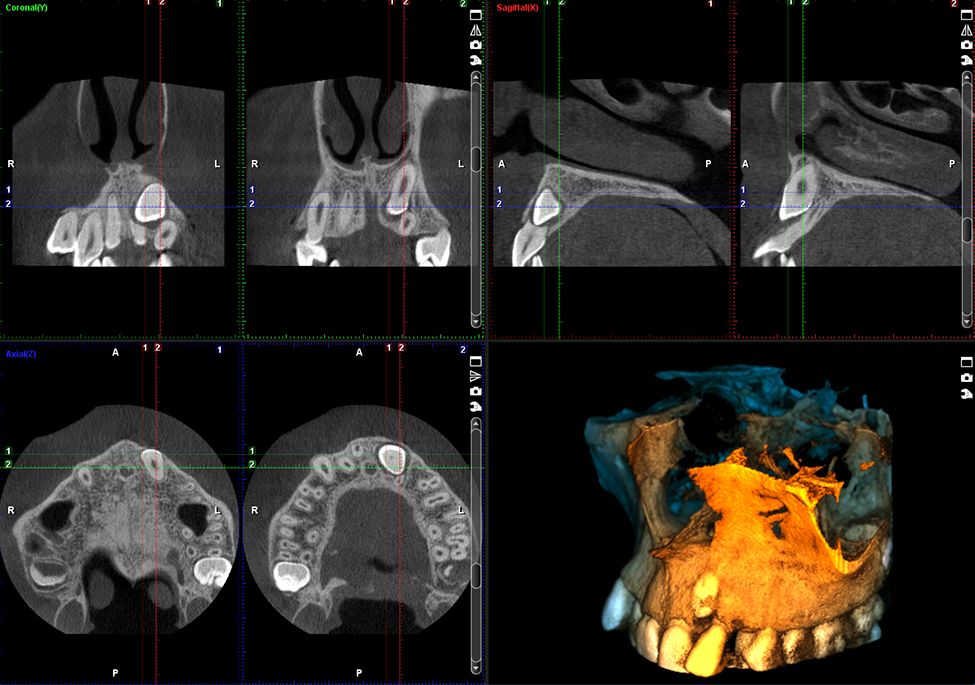

Obrazowanie złożone

Planmeca ProMax 3D Plus, to prawdziwie uniwersalny unit pozwalający na wykonywanie wszystkich rodzajów zdjęć. Poza obrazowaniem 3D, umożliwia także obrazowanie panoramiczne i cefalometryczne – zawsze z zachowaniem optymalnej jakości obrazu.

Obrazy Kliniczne Planmeca ProMax 3D Plus